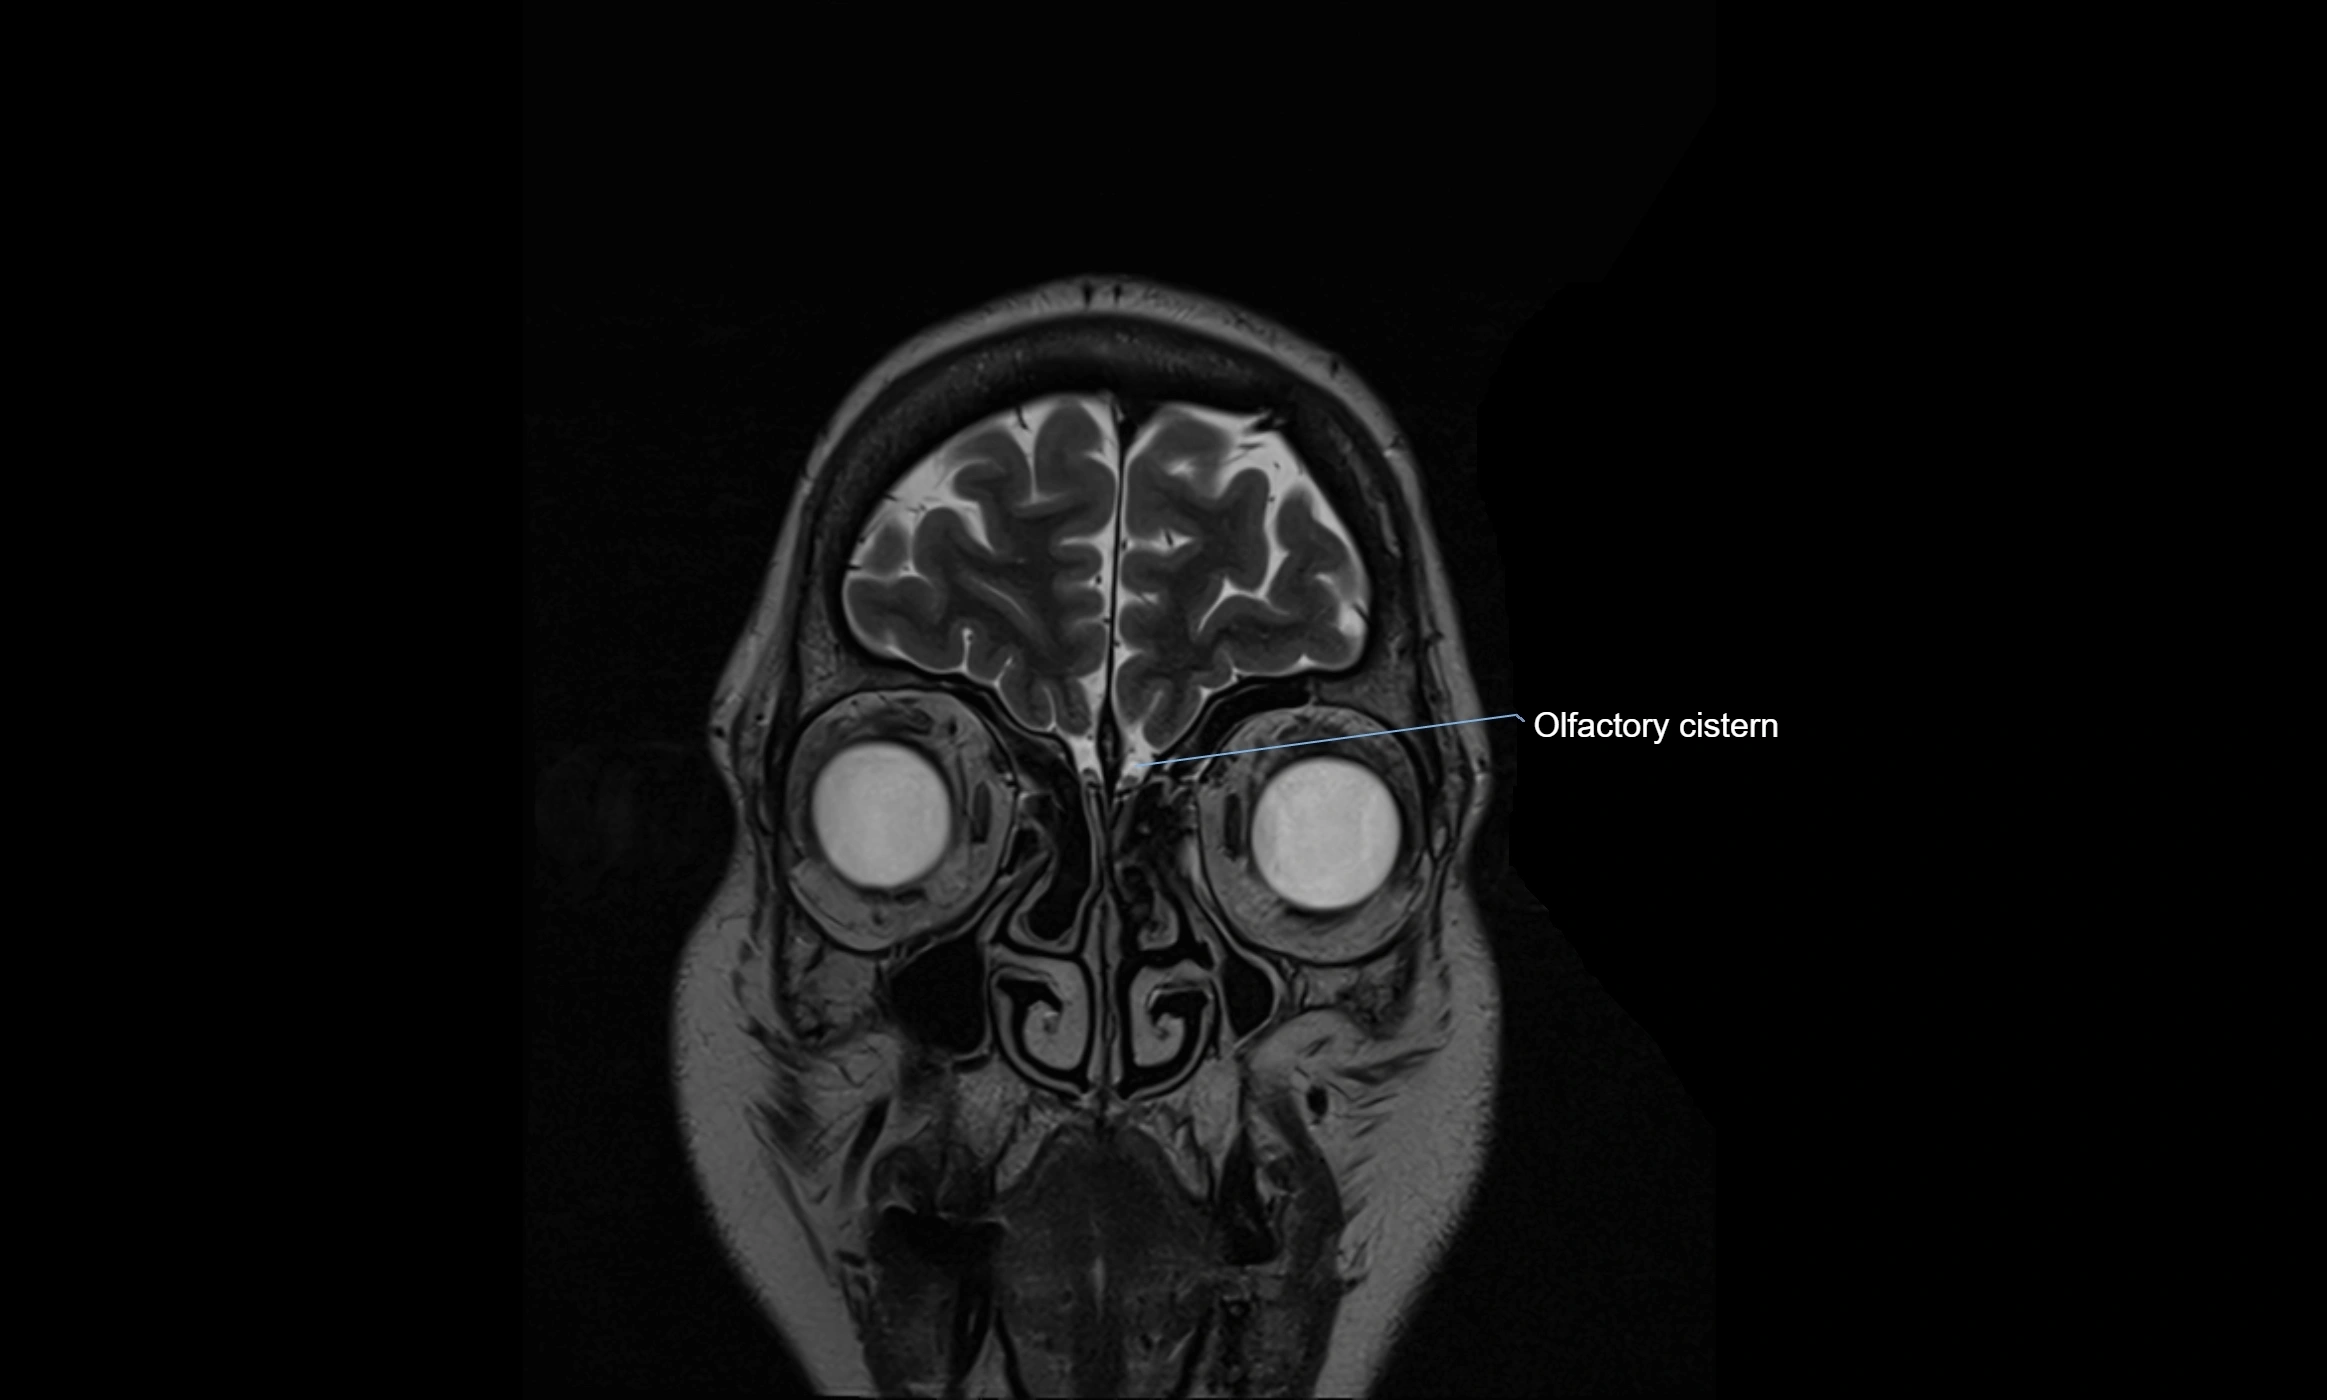

MRI images

image

CT image